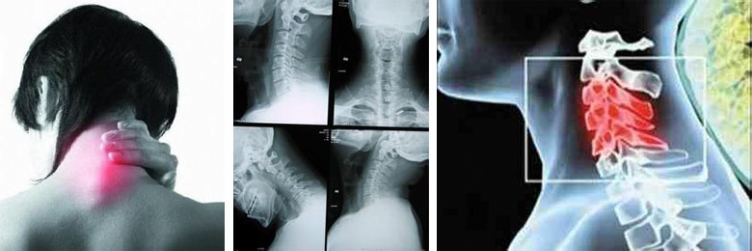

1、颈椎病  康宸堂中医正骨养生>关于我们>成功案例

颈椎病、颈椎错位、颈椎增生、椎间盘突出在长沙康宸堂中医养生馆调好了